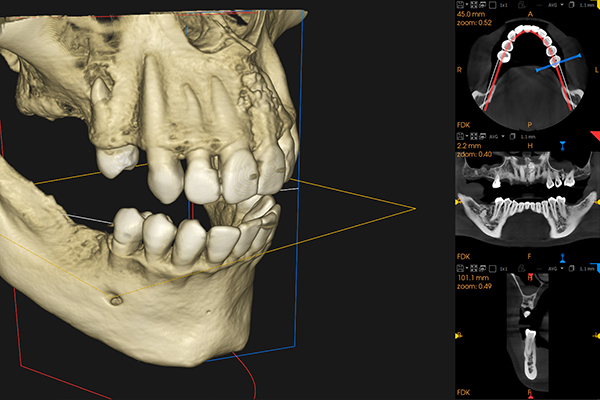

当院では、歯科用CTを使用して、インプラント治療を行う前に、詳細な診断を行います。CTは、断層写真を画像処理することで、あごの骨や周囲の組織を立体的に観察することができる装置で、CTで得られたデータを用いることで、インプラントを埋入する最適な位置や角度をシミュレーションできます。この精密な診断により、治療計画がより正確になり、治療に伴うリスクを最小限に抑えることができます。また、シミュレーションを通じて治療後のイメージを患者さまと共有できるため、安心して治療に臨んでいただけます。

精密検査

治療を進めるために、レントゲンや歯科用CTを用いてお口の状態を詳細に確認します。あごの骨の量や質、インプラントの埋入位置などを適切に評価し、治療計画を立てるためのデータを取得します。この検査が、患者さまに最適なインプラント治療を行うための基礎となります。

精密検査の結果や事前シミュレーションを基に、治療計画を立てます。インプラントの埋入位置や必要な治療期間、費用について詳しく説明し、患者さまに納得していただけるように進めます。治療に対する不安を解消し、患者さまのご希望に沿った治療方法をご提案します。